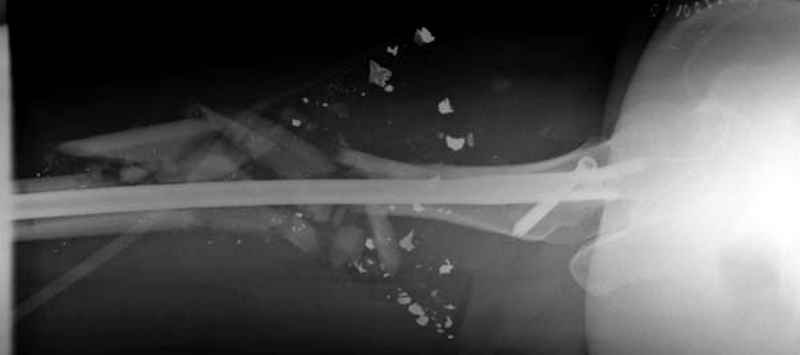

Здесь несколько примеров из нашей практики:

3 такие раны после удаления пули и остатков одежды можно закрыть первично